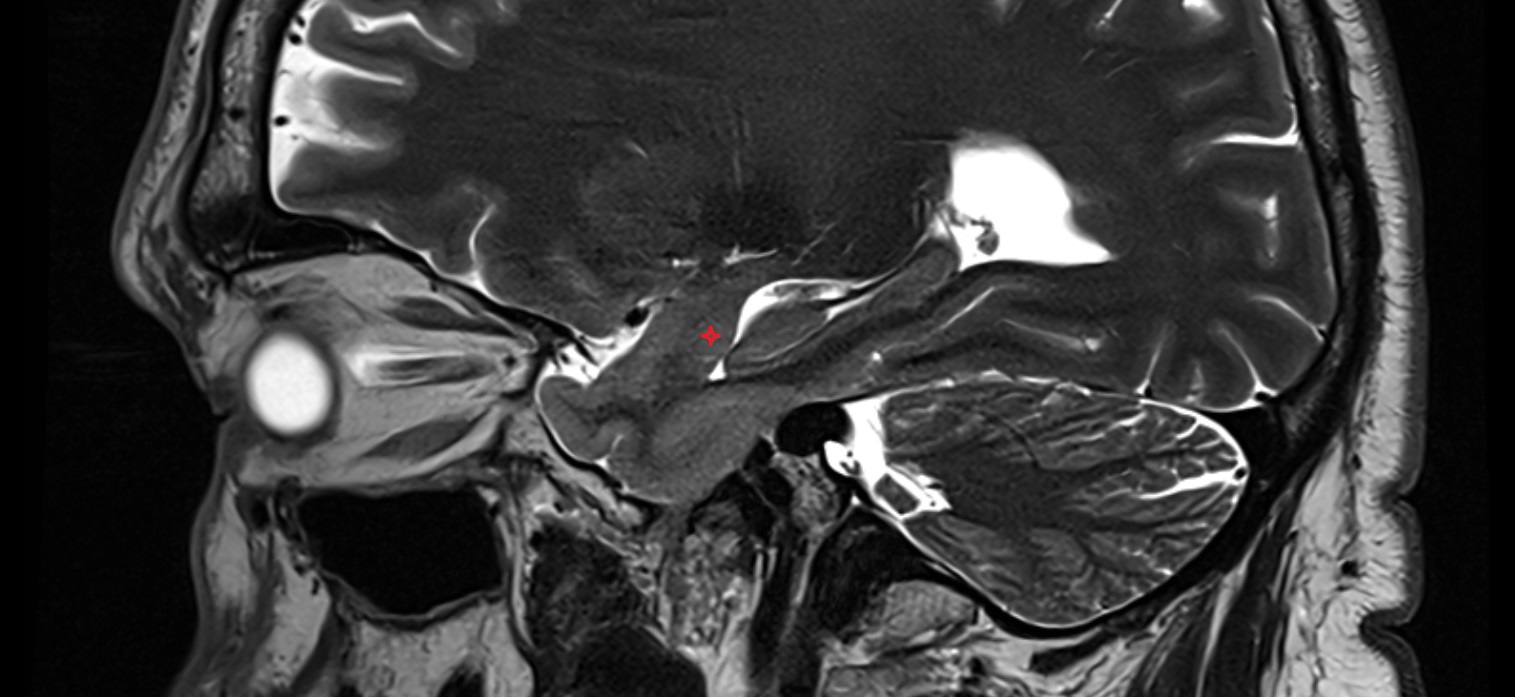

- Hippocampal head

- Head of hippocampus